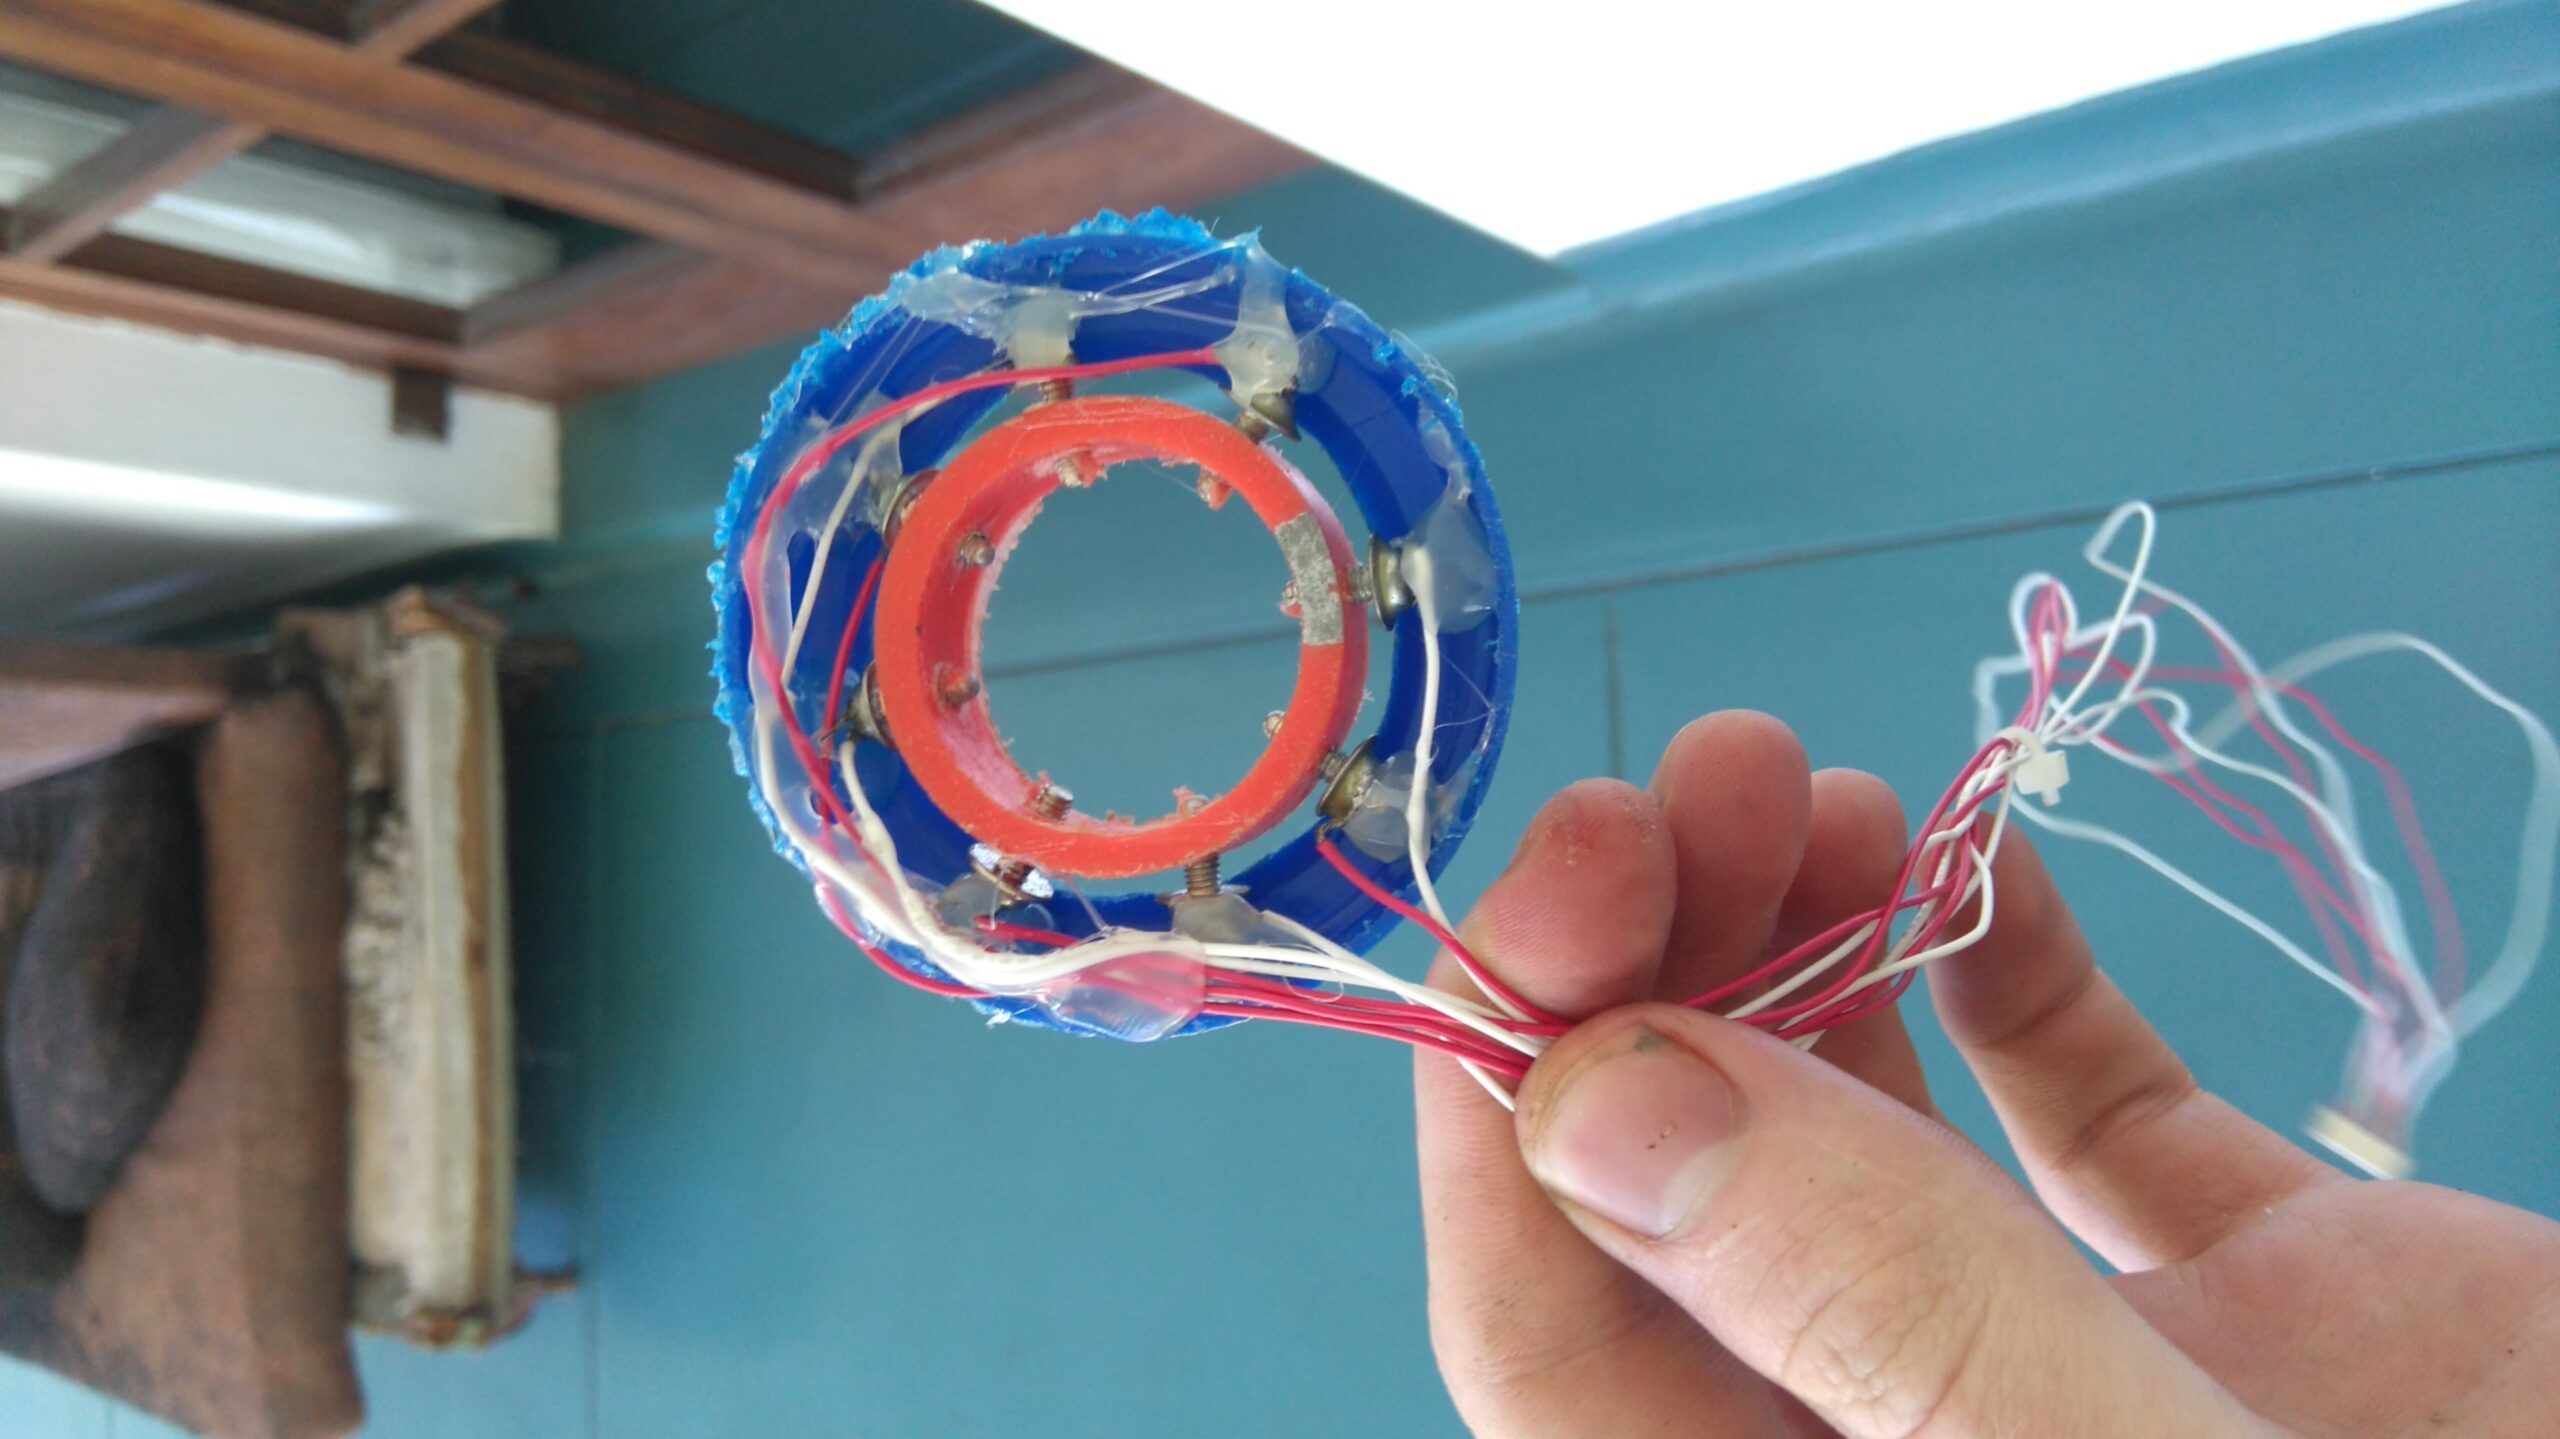

Η αρχή της τομογραφίας εμπέδησης βασίζεται στον υπολογισμό και στις μεταβολές της σύνθετης αντίστασης του ανθρώπινου σώματος σε μια εγκάρσια διατομή, η οποία μετράται με τη βοήθεια 16 ηλεκτροδίων. Τα ηλεκτρόδια είναι τοποθετημένα γύρω από το επίπεδο της εγκάρσιας διατομής που πρόκειται να μελετηθεί, ενώ η ανασύνθεση της εικόνας αναπαράγεται σε monitor το οποίο διαθέτει ο τομογράφος. Όταν εφαρμόζεται εναλλασσόμενο ρεύμα γνωστής έντασης μεταξύ δύο ηλεκτροδίων δημιουργείται ηλεκτρική δραστηριότητα μεταξύ τους.

Η αρχή της τομογραφίας εμπέδησης βασίζεται στον υπολογισμό και στις μεταβολές της σύνθετης αντίστασης του ανθρώπινου σώματος σε μια εγκάρσια διατομή, η οποία μετράται με τη βοήθεια 16 ηλεκτροδίων. Τα ηλεκτρόδια είναι τοποθετημένα γύρω από το επίπεδο της εγκάρσιας διατομής που πρόκειται να μελετηθεί, ενώ η ανασύνθεση της εικόνας αναπαράγεται σε monitor το οποίο διαθέτει ο τομογράφος. Όταν εφαρμόζεται εναλλασσόμενο ρεύμα γνωστής έντασης μεταξύ δύο ηλεκτροδίων δημιουργείται ηλεκτρική δραστηριότητα μεταξύ τους.